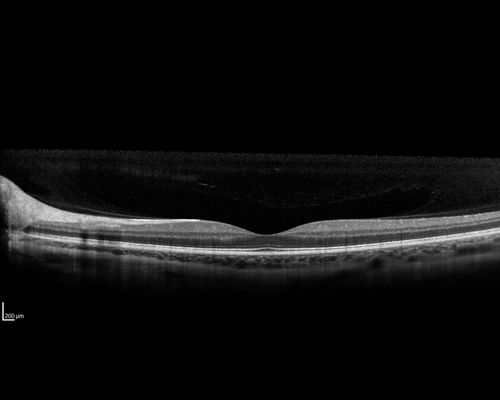

Multifocal Choroiditis - Pneumocystis - aspergillis - cryptococcus

31 year old male with anaplastic astrocytoma on chemotherapy with mild vision loss in the right eye.  LP did not reveal organism.  He was placed on a trial of anti-fungal medications and lost to follow-up